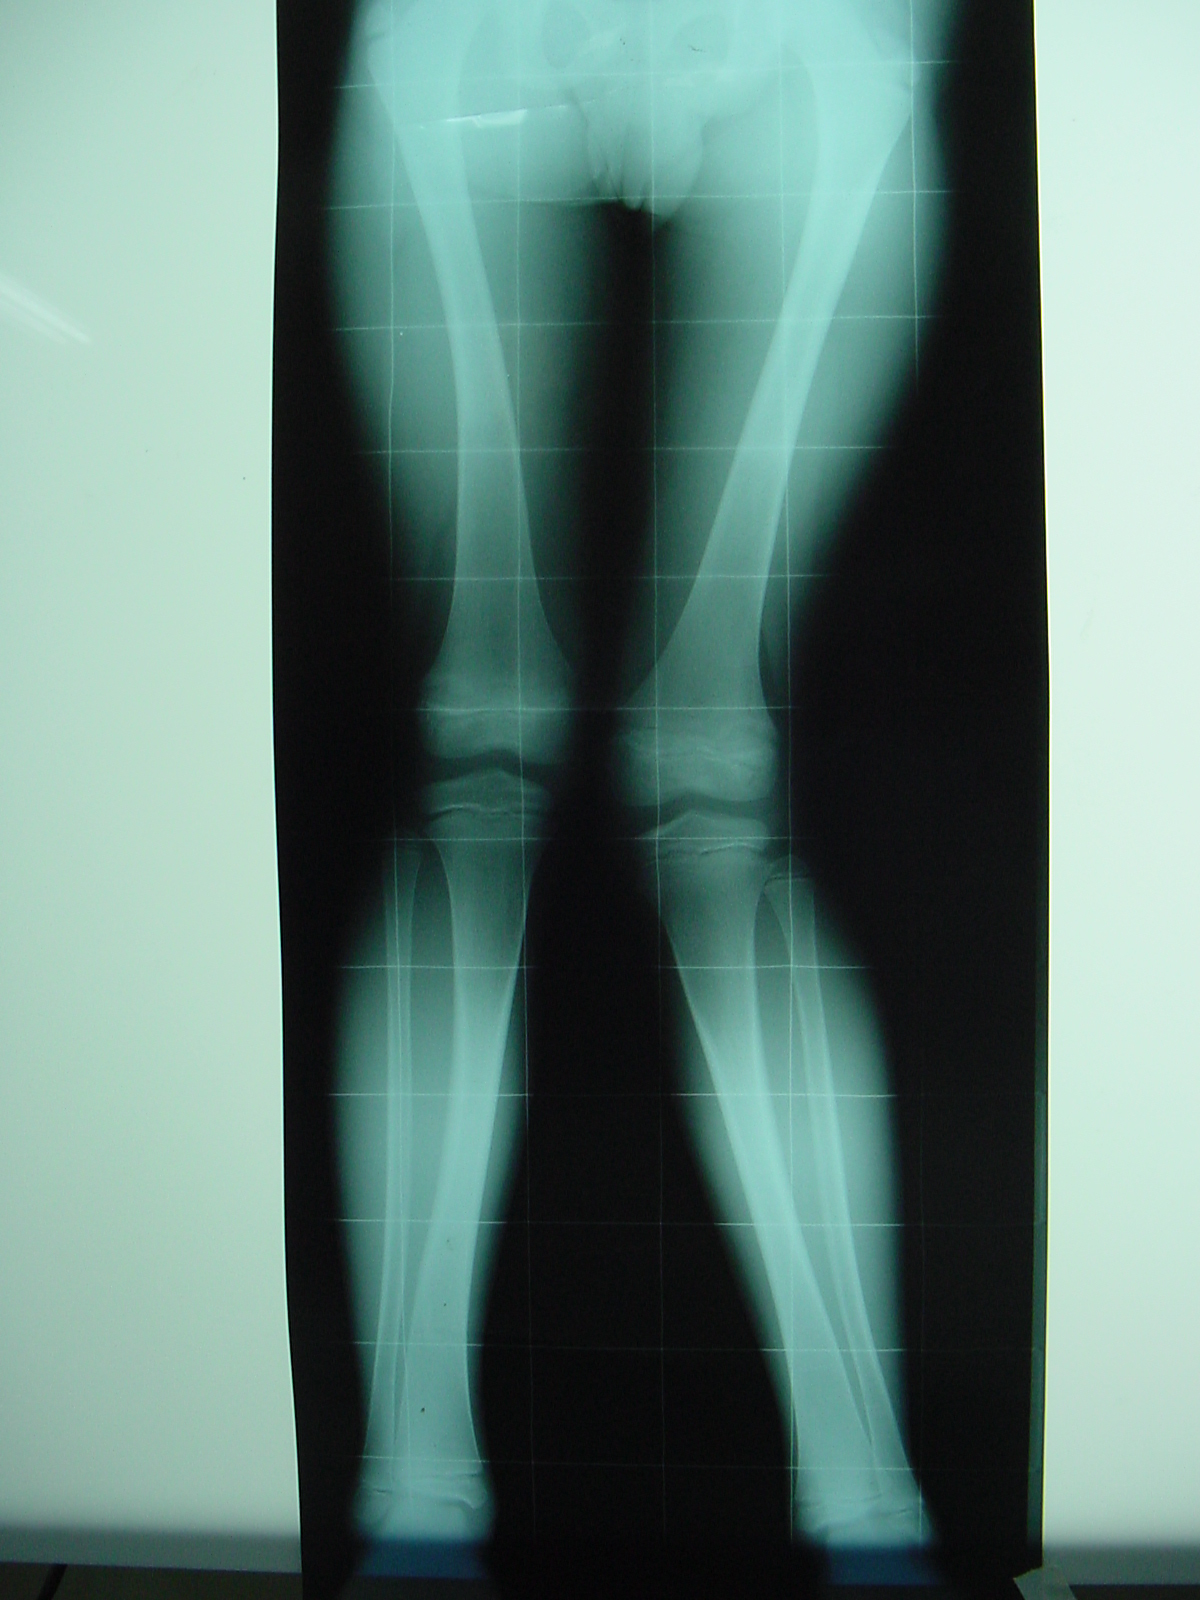

Modulación del crecimiento en osteodistrofia renal. [Growth modulation in renal osteodystrophy]

3. Barrett IR, Papadimitriou DG. Skeletal disorders in children with renal failure. J Pediatr Orthop 1996;16(2):264-72.

4. Oppenheim WL, Fischer SR, Salusky IB. Surgical correction of angular deformity of the knee in children with renal osteodystrophy. J Pediatr Orthop 1997;17:41-9.

5. Castañeda P, Urquhart B, Sullivan E, Haynes RJ. Hemiepiphysiodesis for the correction of angular deformity about the knee. J Pediatr Orthop 2008;28(2):188-91.

14. Stevens P, Klatt JB. Guided growth for pathological physes: radiographic improvement during realignment. J Pediatr Orthop 2008;28(6):632-9.